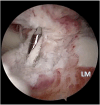

Graft-tunnel mismatch (GTM) is a known technical challenge that can occur with anterior cruciate ligament reconstruction when using a patellar tendon autograft. Two-incision anterior cruciate ligament reconstruction is a well-established technique with excellent outcomes and can serve as an excellent tool to prevent GTM. Traditionally, 2-incision femoral tunnel drilling has been performed using an over-the-top guide through a lateral incision, but more modern retrograde reamer guides can allow this to be done percutaneously. We detail how a minimally invasive 2-incision femoral tunnel drilling technique can be used in patients with patellar tendon lengths that are longer than average to avoid GTM.